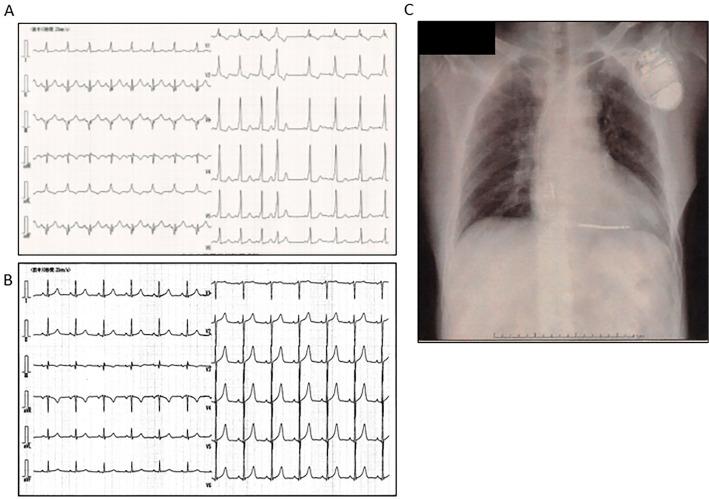

We herein report a case of a 53-year-old man who survived cardiac arrest due to ventricular fibrillation (VF). When admitted to the hospital, his 12-lead electrocardiogram did not show Brugada-like ST elevation, early repolarization or delta-wave, in any leads. During the treatment of hypothermia, the manifestation of delta-wave was documented, which disappeared after the cessation of this treatment. A cardiac evaluation showed no structural heart disease, and electrophysiology studies did not demonstrate conduction via accessary pathway. Although the etiology of VF could not be determined, the most probable diagnosis was idiopathic VF. The patient was fitted with an implantable cardioverter-defibrillator.

我们在此报告一例53岁男性因心室颤动(VF)导致心脏骤停后存活的病例。入院时,他的12导联心电图在任何导联均未显示出类似Brugada综合征的ST段抬高、早期复极或δ波。在低温治疗期间,记录到了δ波的表现,该表现于治疗停止后消失。心脏评估显示无结构性心脏病,电生理研究未证实存在经附加旁路的传导。尽管VF的病因无法确定,但最可能的诊断为特发性VF。该患者植入了植入式心脏复律除颤器。